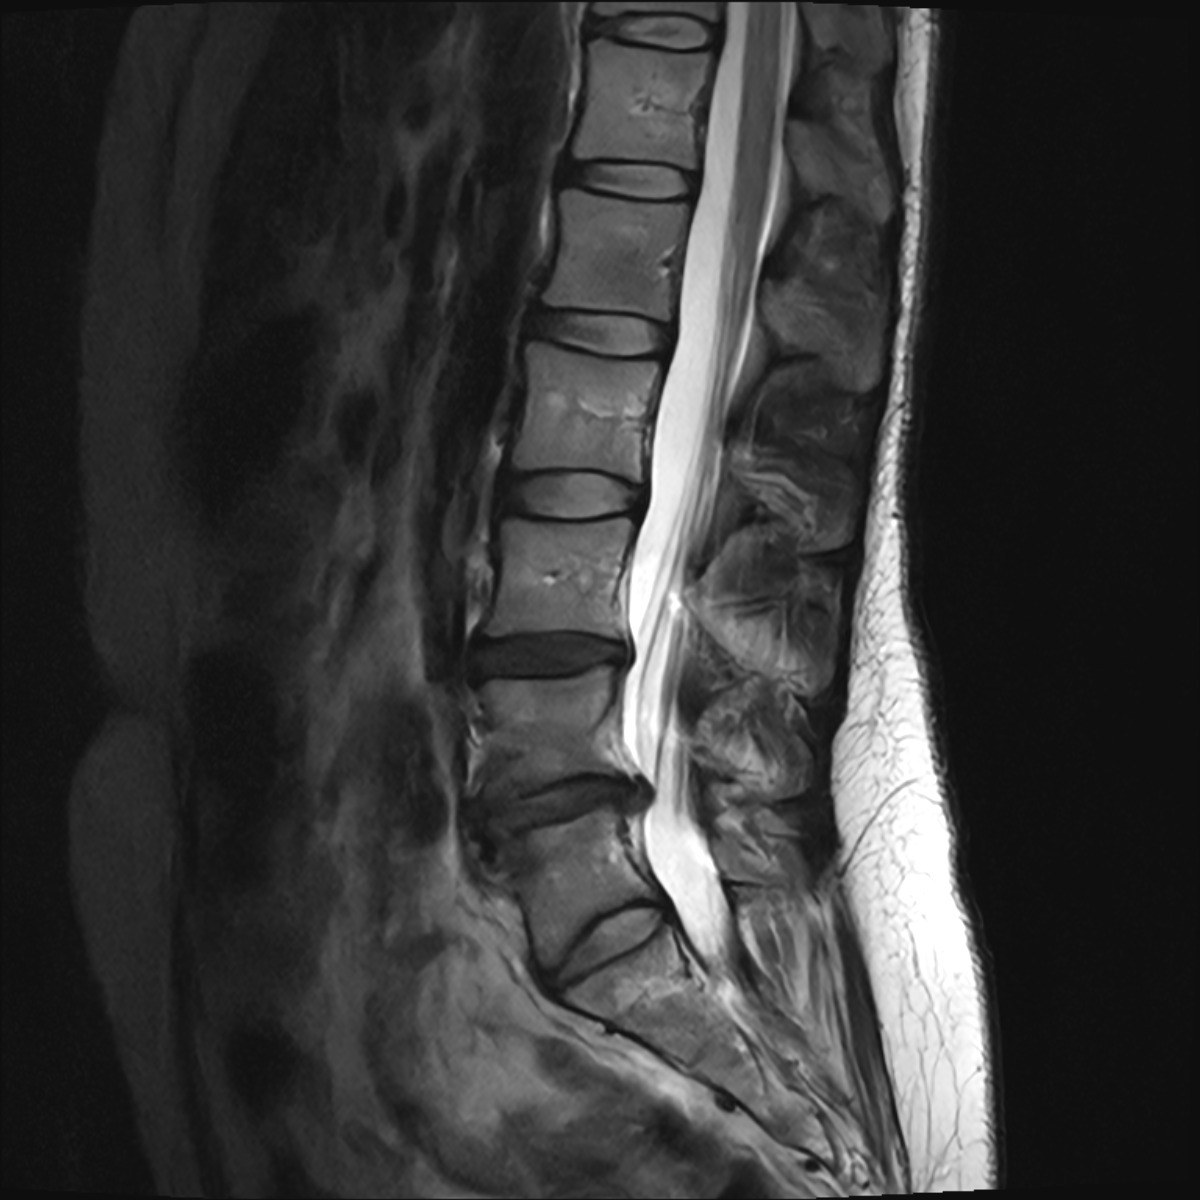

My L4-L5 disc has herniated and is pressing on the sciatic nerve root, causing constant, severe nerve pain that radiates down my left leg. It’s a deep, burning pain that makes standing, sitting, or walking for long periods nearly impossible. I’ve been in pain for months, trying every conservative treatment available — rest, physical therapy, medications, and two rounds of steroid injections — but at this point, surgery is my only option to find relief and prevent permanent nerve damage.

- MRI imaging ($350)